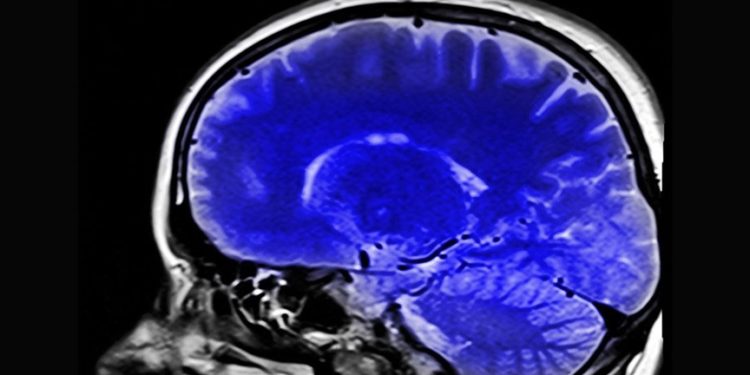

Araştırmacılar, katılımcıların kronik ağrı düzeylerine bağlı olarak tepkilerinin yansıdığı düşünülen beynin “anterior singulat korteks (ACC)” ve “orbitofrontal korteks (OFC)” adlı iki bölgesindeki aktivite değişikliklerine odaklandı.

Üçü inme sonrası, biri de kesilmiş olmasına rağmen sanki uzvu varmış gibi ağrı şikayeti bulunan katılımcılara ACC ve OFC’lerindeki aktivite değişikliklerini tespit etmeyi hedefleyen elektrotlar, cerrahi müdahaleyle yerleştirildi.

Katılımcılardan gün içinde birkaç kez yaşadıkları acıyı nasıl derecelendirdikleri, duygusal olarak nasıl hissettirdiği gibi soruları yanıtlamaları istendi, bu sırada hastaların ACC ve OFC’lerindeki aktivitenin anlık görüntüleri kaydedildi.

Shirvalkar, akut ağrılar tecrübe edildiğinde MR taramalarıyla beynin ACC ve OFC bölgelerindeki yansımalarını görebildiklerini belirterek, buradan yola çıkarak beyindeki ACC ve OFC bölgelerinin kronik ağrı oluştuğunda nasıl tepki verecekleriyle ilgilendiklerini kaydetti.